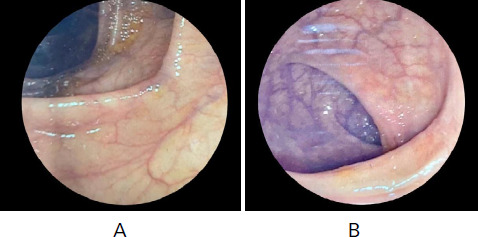

In Southeast Asia, the higher prevalence of Intestinal tuberculosis (TB) challenges the diagnosis of Crohn's disease (CD) due to their overlapping symptoms. This case involves a 25-year-old male misdiagnosed with Intestinal tuberculosis presenting with abdominal pain, weight loss, and bowel ulceration. Recurrence after anti-tubercular therapy led to further investigation paving to right hemicolectomy and histopathological analysis confirming Crohn's disease. This case highlights the complexity of the diagnosis of Crohn's disease in tuberculosis-prevalent areas, stressing the clinical importance, advanced diagnostics tools, and multidisciplinary approach for effective intervention.